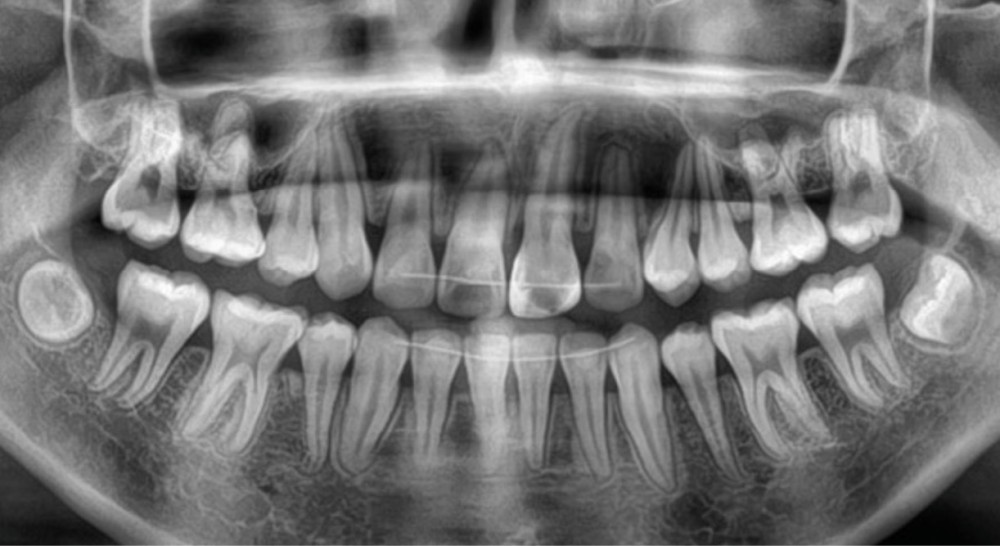

Une patiente âgée de 12 ans se présente en consultation, motivée par la position de son incisive centrale maxillaire, décrite comme « en avant », marquée par une dyschromie et une mobilité de grade 2 selon Muhlemann. L’examen clinique montre l’absence de 23 sur l’arcade, une dysharmonie dents-arcade marquée, un surplomb accentué, et une déviation des milieux inter-incisifs, conséquence du comblement spontané de l’espace de 23. L’ensemble s’inscrit dans un contexte de Classe I d’Angle molaire. L’orthopantomogramme révèle l’inclusion de 23, associée à une résorption radiculaire étendue aux deux tiers de 21. La 22 ne présente aucune altération visible.

La patiente, de profil normodivergent, présente une Classe I squelettique sans troubles fonctionnels (fig. 1-8).